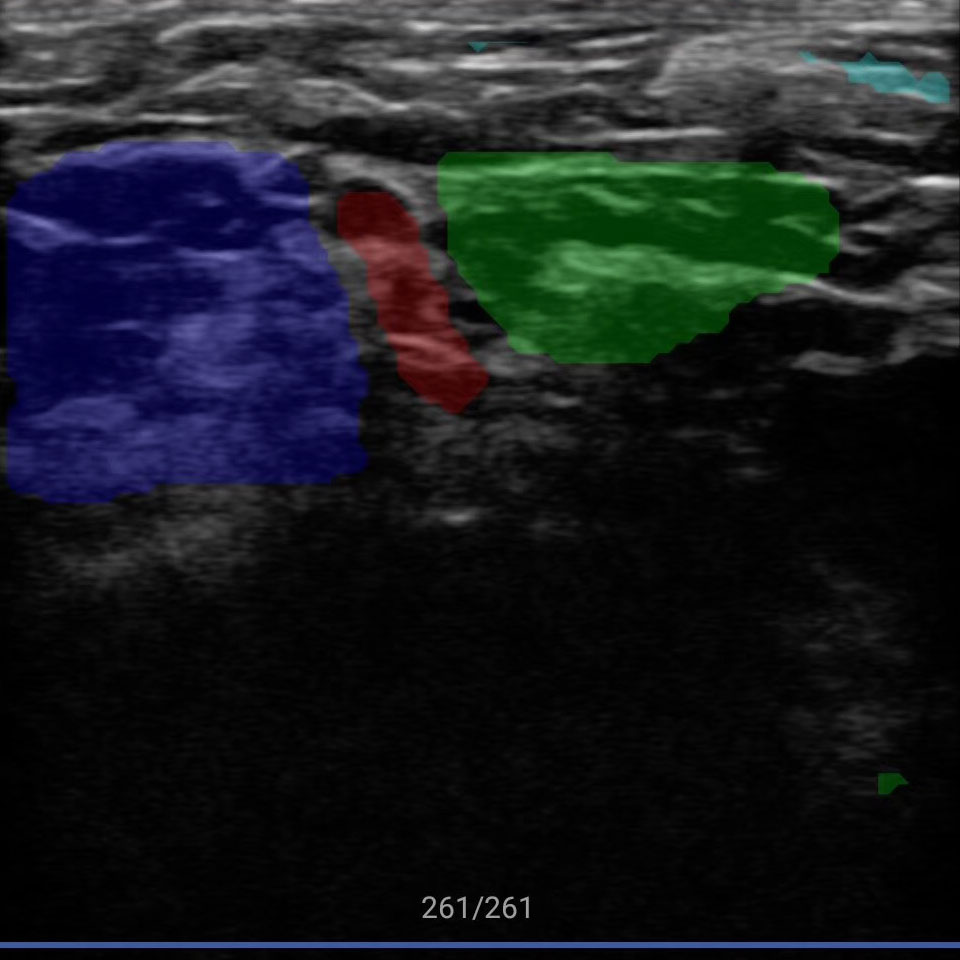

传统超声的多普勒测量非常繁琐,需要设置大量参数手工操作,新名医全球首创一键多普勒测量,AI自动找到血管、自动计算出12项血流动力学参数,让复杂的超声变得像血压计一样,读数就可知道异常,提示粥样动脉硬化、血管狭窄、易损斑块、流速异常等多种脑梗风险。